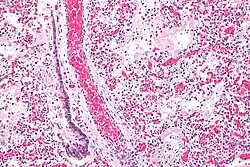

В основе ОРДС лежит диффузное воспаление лёгких. В этом процессе выделяют 3 фазы: экссудативная, пролиферативная и фибротическая[8].

В экссудативную фазу в ответ на воспаление выделяются цитокины и другие провоспалительные вещества, которые активируют альвеолярные макрофаги и циркулирующие нейтрофилы. В свою очередь, активированные нейтрофилы прикрепляются к эндотелию лёгочных капилляров и высвобождают содержимое своих цитоплазматических гранул (протеазы и токсические метаболиты кислорода)[10]. Это приводит к повреждению эндотелия капилляров и эпителия альвеол, нарушая альвеолярно-капиллярный барьер. В результате экссудат проникает в лёгочную паренхиму и альвеолярное воздушное пространство. Нарушается газообмен и возникает гипоксия[11]. Также возможно повреждение альвеолоцитов II типа, которые отвечают за образование сурфактанта. При этом происходит спадение альвеол, снижение растяжимости лёгких и внутрилёгочное шунтирование. Кроме того, развивается лёгочная гипертензия в результате внутрисосудистой обструкции тромбами, спазма лёгочных сосудов из-за гипоксии и действия некоторых воспалительных медиаторов (тромбоксан, лейкотриены и эндотелин)[12].

В пролиферативную фазу у большинства пациентов происходит восстановление лёгких: удаляется экссудат, нейтрофильная инфильтрация сменяется лимфоцитарной. Пролиферируют альвеолоциты II типа, которые образуют новый сурфактант и дифференцируются в альвеолоциты I типа. Но несмотря на такие улучшения, у многих больных сохраняется одышка, тахипноэ, гипоксемия[8]. У некоторых пациентов процесс переходит в фибротическую фазу. Накопленный в лёгких фибрин подвергается ремоделированию и может вызывать фиброз[13].